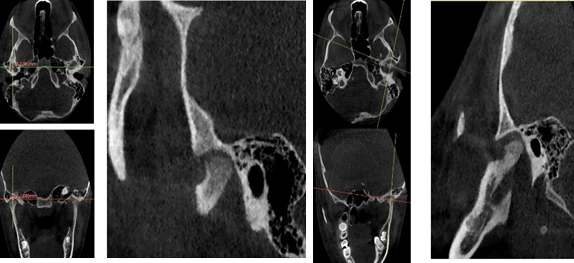

El análisis de discrepancia se realizó sobre los modelos de estudio obteniendo una discrepancia superior de - 4mm y una discrepancia inferior de -1.8 mm (G). En la ortopantomografía se observa que el seno maxilar izquierdo aparece velado, presencia de los 4 gérmenes de los terceros molares, cornetes hipertróficos, no se visualiza ensanchamiento del ligamento periodontal, no existen patologías periapicales (H). Los estudios cefalométricos que se realizaron fueron Rickkets, Jaraback y Steiner, obteniendo como resumen: patrón esqueletal Clase II por protrusión maxilar, a nivel de incisivos: protrusión y proinclinación del incisivo superior e inferior, VERT: +0,69 dándonos un patrón facial: braquifacial suave, en las esferas rotacionales de Jarabak: 54% indicándonos una tendencia a crecimiento rotacional posterior (I).

A través de los cortes tomográficos (Figura 3) se pudo observar que la rama mandibular derecha medía 43.85 mm y la izquierda 39.53 mm dando una diferencia de 4.34 mm lo que evidencia que la asimetría que presenta la paciente es a causa de la discrepancia de tamaño de las ramas mandibulares (A).

En el corte a nivel de la articulación temporomandibular izquierda se observó un aplanamiento del cóndilo con áreas de cambios osteoartríticos leves (B); en la articulación temporomandibular derecha el cóndilo se encuentra con una severa osteoartritis que muestra una imagen hipodensa a nivel condilar compatible con un quiste subcondral (C).

Diagnóstico de ATM: La paciente presenta una displasia discal sin reducción bilateral.

Plan de tratamiento: Debido a todo lo expuesto se decidió colocar un aparato de avance mandibular tipo monoblock para recapturar el disco. Para ello se inició con la realización de una mordida constructiva para la confección del aparato, se llevó a una coincidencia de las líneas media y un adelantamiento mandibular de 3 mm (Figuras D, E y F). Posteriormente se envió los registros para la confección del dispositivo de avance mandibular tipo monoblock (Klammt Clase II) que fue instalado en marzo del 2023 constatando de que se encuentre totalmente adaptado (G), las indicaciones de uso fueron más de 20 horas al día aconsejando que la paciente se lo retire únicamente para comer y para el aseo respectivo. Los controles se realizaron a las 2 semanas y después con una frecuencia mensual durante 12 meses.